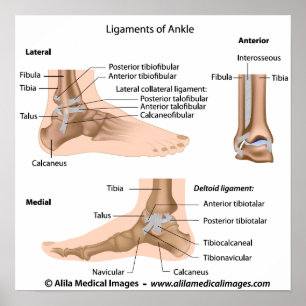

Knöchelligamente, beschriftet Zeichnung Poster

PreisCHF 45.30